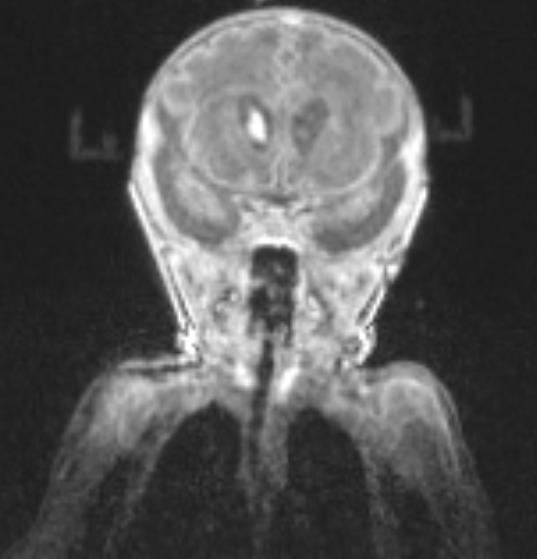

Cristina Felice Civitillo (1), Frédéric Jonathan Leis (2), Céline Habre (3), Francisca Barcos- Munoz (1) (1) Néonatologie et soins intensifs pédiatriques, Département Femme Enfant et Adolescent, HUG, Hôpitaux Universitaires de Genève (2) Atelier 3Durable, Université de Genève (3) Département de Diagnostic, Service de Radiologie, HUG, Hôpitaux Universitaires de Genève

IRM de vrais patients → Voies aériennes (bouche-trachée)

Différents âges gestationnels (24 - 44 SA) et différents poids (400g - 4kg)

Impression 3D multi-matériel

Création simulateur haute fidélité pour intubation